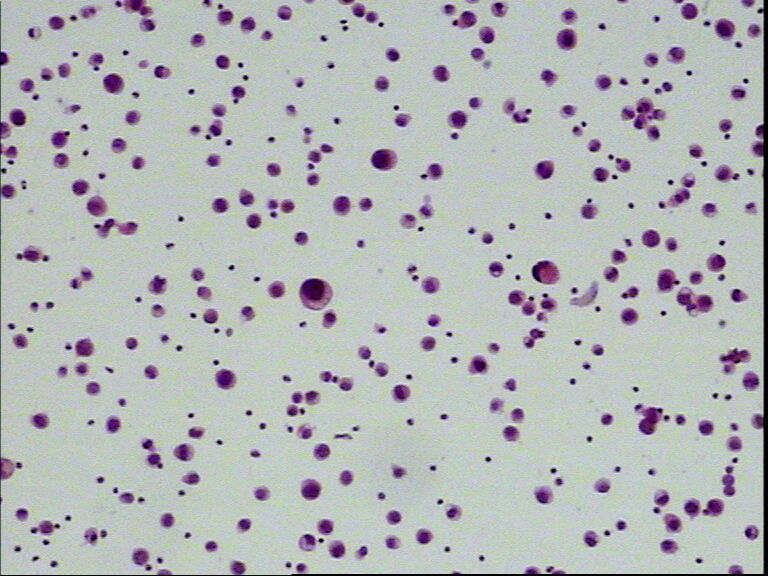

男性,80岁,腹水待查

• 男性,80岁,腹水待查图1

图1

间皮细胞

恶性细胞,需做IHC。

细胞有异型

低分化腺癌要重点考虑!

涂片中可见淋巴细胞、中性粒细胞及间皮细胞,个别核大深染的细胞是增生的间皮细胞,不是癌细胞,这种细胞很容易和癌细胞混淆,下诊断时一定要加小心。

细胞有异形,且胞浆内有空泡,需结合临床检查或做免疫组化已确诊。

考虑增生性间皮细胞

腺癌?,细胞形态暂时不讨论,做IC,会比讨论来的更实在。

可疑癌细胞,确实需要做IHC。